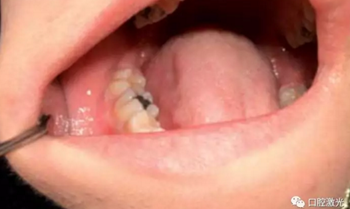

齦瘤指的是任何位于牙齦部的良性纖維瘤病變。齦瘤通常呈粉紅色,雖然為良性,但會隨牙齦一同生長,有時會因體積過大而包裹一顆或多顆牙齒。目前,齦瘤的具體病因上不可完全清楚,一般采用外科手術(shù)切除是被認為是安全的,其中就包含利用口腔激光進行切除。口腔激光擁有許多的波長,都可以用到齦瘤切除等軟組織手術(shù)中,并且擁有快速凝固和高效滅菌的特點。

本文收集了多位年齡在14至50歲的齦瘤患者,均活檢診斷后確認。所有手術(shù)均在門診完成,全部使用半導(dǎo)體口腔激光。其功率設(shè)置為:4至6W,連續(xù)模式。光纖芯徑300微米。所有的患者都在術(shù)后1周,4周,6個月以及1年時間復(fù)診,評估激光手術(shù)的長期效果。

在治療前,患者、醫(yī)生及助手均佩戴正確的防護眼鏡,并且對患處進行拍照記錄。隨后使用2%的利多卡因 1cc進行浸潤麻醉。激光器設(shè)置完畢后,采取外切的手法,利用鑷子將齦瘤拉伸后,從其根部進行外切。手術(shù)后無需縫針,并對切除物進行病理學(xué)檢查。檢查結(jié)果確認為纖維瘤。整個手術(shù)過程通常為4至6分鐘。建議患者術(shù)后冰敷以減少水腫發(fā)生。